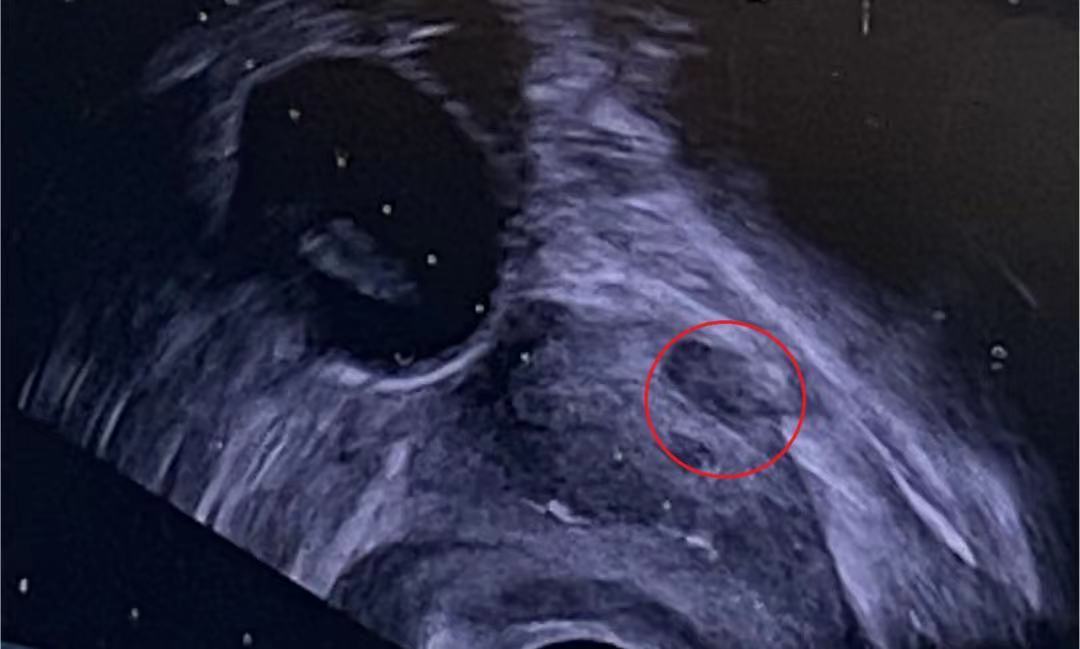

经研究,科室决定为该患者行经会阴前列腺靶向穿刺术。以0.5cm可疑病灶为靶病灶,进行超声下精准定位(图1),经会阴进针,以适当角度绕过耻骨后,再向前列腺腹侧调整方向继续进针,在超声引导下抵达病灶附近。贴紧靶病灶穿刺活检(图2),成功取得肿瘤组织样本,并于术后病理检测中确认为早期前列腺癌。该患者发现早、病灶小、未发生临近器官侵犯和远处转移,具备根治手术的条件,计划行腹腔镜下前列腺癌根治术,以彻底切除恶性肿瘤,使患者重获健康。

图1:精准定位